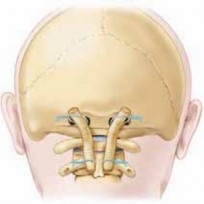

Gallie Technique

2. After exposing the posterior arch of the atlas and spinous process of the axis, the two free ends of a single 16-or 18-gauge wire are passed beneath the posterior arch of the atlas from a superior-to-inferior direction.10

3. The free ends are passed beneath the posterior arch and are brought around superiorly to loop on themselves.

4. A rectangular corticocancellous autograft is harvested from the posterior iliac spine.

1. A notch is created at the distal part of the graft. This part will be placed across the spinous process of the axis.

5. The notched graft is placed between the posterior portion of the arch of C1 and the posterior spinous process of C2.

6. Now the free ends of the looped wire are brought down over the graft and passed below the spinous process.

7. The free ends of the wire are tightened and twisted over the graft (

TECH FIG 3

).

60. Morcellized bone grafts may be packed into the fusion area to add additional support.

61. Intraoperative fluoroscopy is necessary to check for satisfactory reduction and alignment of C1–C2.

Mah Modified Gallie Technique

62. In 1989, Mah described a modification of the Gallie technique.13

63. All the steps of the Mah technique are similar to the Gallie technique, except that a threaded Kirschner wire is placed through the spinous process of the C2 and both ends of the Kirschner wire are cut, leaving about 2.5 cm of the total wire.

64. The free ends of the looped wire are brought down below the free ends of the threaded Kirschner wire (

TECH FIG 4

65. The free ends of the wire are tightened, secured, and crimped over the graft. TECH FIG 3 • Gallie technique for atlantoaxial arthrodesis.TECH FIG 4 • Mah modified Gallie technique for atlantoaxial arthrodesis.